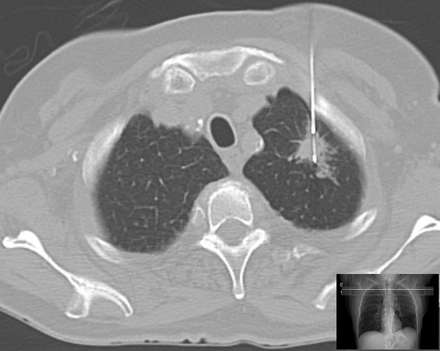

С 2005 по 2010 г. 107 больным была произведена в отделении лучевого и хирургического лечения заболеваний торакальной области МРНЦ Минздравсоцразвития России трансторакальная пункционная биопсия под контролем компьютерной томографии. Возраст больных варьировал от 20 до 86 лет (в среднем 58,5 года). Каждый пациент был проинформирован об особенностях предстоящей процедуры и возможных осложнениях. Исследование проводилось под местной анестезией в горизонтальном положении больного на столе компьютерного томографа. Место прокола грудной стенки избиралось индивидуально в зависимости от расположения очага, пути прохождения иглы, удобства пункции и снижения риска потенциальных осложнений. Положение иглы контролировалось КТ в различные временные этапы выполнения процедуры.

При проведении трансторакальной биопсии легкого получить материал для дальнейшего исследования удалось у 103 пациентов. В 4 наблюдениях проведение пункции оказалось неудачным и морфологический материал не был получен по причине развившегося пневмоторакса (3 наблюдания), не позволившего локализовать иглу в опухоли, и в связи с плотной консистенцией опухоли и ее малым размером (1). Процедура пункции вместе с предварительной КТ-разметкой занимала от 15 до 35 мин. Как правило, для локализации иглы в опухоли было достаточно одного прокола грудной стенки (рис. 2),Рисунок 2. Компьютерная томограмма больного С. Конец иглы локализован в центре опухоли правого легкого. в редких наблюдениях эта процедура осуществлялась повторно.![]()